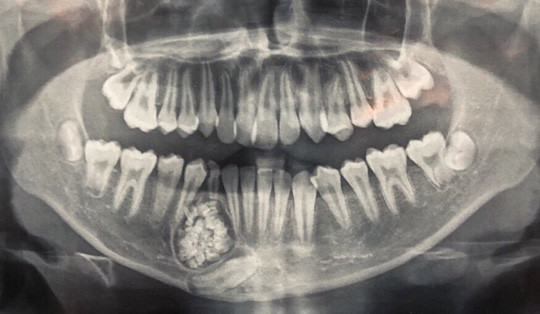

| U răng với gần 100 chiếc răng nhỏ - ảnh: Bệnh viện Đa khoa Khánh Hòa cung cấp. |